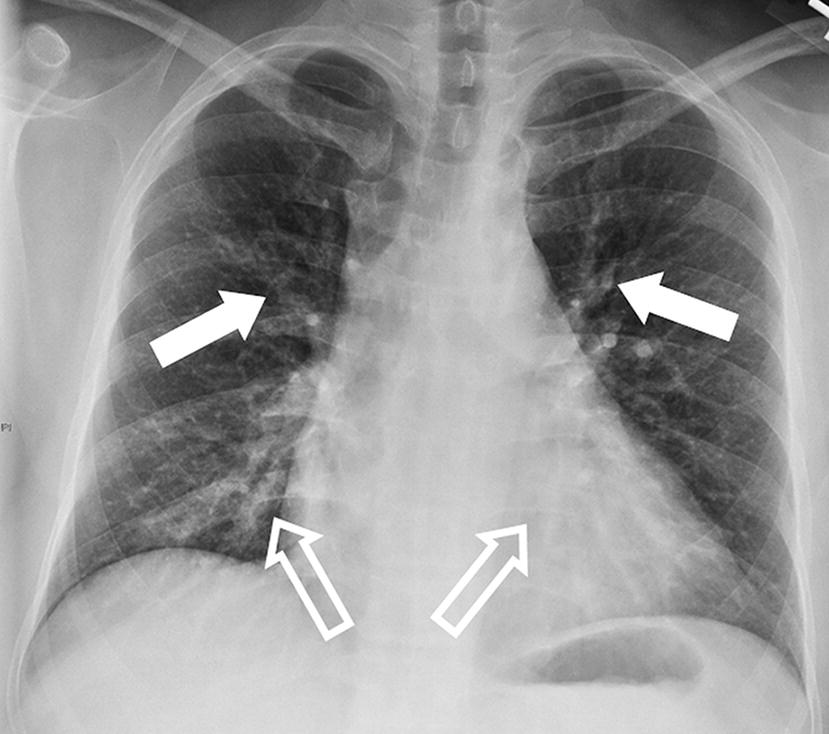

Cyanosis refractory to oxygen administration. Alveoli filled with protein rich edema. In contrast, noncardiogenic pulmonary edema is caused by various disorders in which factors other than elevated pulmonary capillary pressure are responsible for.

Acute pulmonary oedema is a very frightening experience for the patient and represents a genuine medical emergency. This fluid makes it difficult for the lungs to function (to exchange oxygen and carbon dioxide with cells in the bloodstream). Learn what distinguishes pulmonary edema from pneumonia. A useful tool to differentiate acute cardiogenic pulmonary edema from acute respiratory distress syndrome.